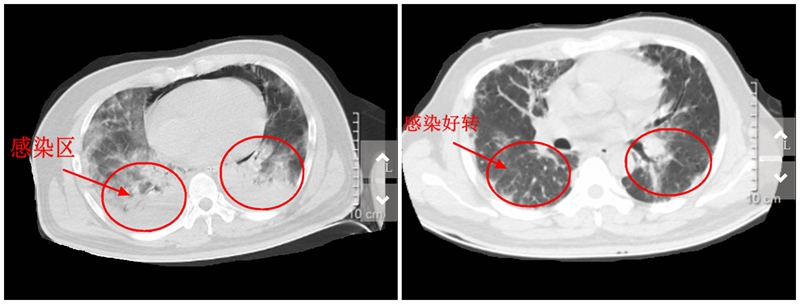

胸部CT检查竟发现小吴的肺部感染严重,被诊断为重症肺炎,住入EICU抢救。

【感染前后CT对比照】